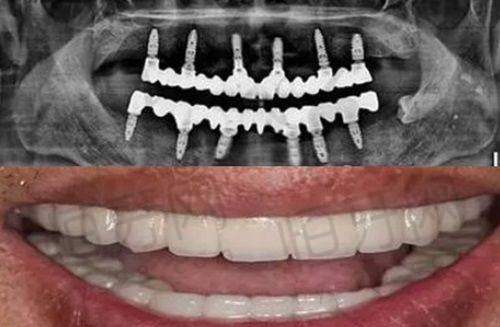

该门诊部的特色项目丰富多样,涵盖了多个口腔诊疗领域。口腔种植是其特色项目之一,由种植科副主事级医师坐诊,能够为患者提供专精、精细的种植方案。对于那些牙齿缺失的患者来说,口腔种植可以帮助他们修复牙齿的功能和美观。牙齿正畸同样出色,正畸科副主事级医师会根据患者的牙齿情况,制定个性化的正畸方案,帮助患者拥有整齐美观的牙齿。美学修复项目可以改善牙齿的外观,让牙齿更加洁白、整齐,提升患者的笑容魅力。儿童口腔项目则专门针对儿童的口腔特点,提供预防、治疗等一系列服务,培养儿童良好的口腔卫生习惯。此外,门诊部还提供其他常规口腔诊疗服务,满足患者的各种口腔需求。

门诊部拥有精良的诊疗设备,这些设备为正确诊断和有效治疗提供了有力支持。口腔CT设备可以清晰地呈现口腔内部的结构,帮助医生更正确地了解患者的牙齿、骨骼情况,为口腔种植、正畸等治疗提供严谨的依据。数字化牙片机能够快速、清晰地拍摄牙齿的影像,方便医生及时发现牙齿的问题,如龋齿、牙髓炎等。超声洁牙机利用超声波的高频振动,能够有效地去除牙齿表面的牙结石、菌斑等,清洁成效好,而且对牙齿的损伤较小。激光治疗设备在口腔治疗中也发挥着重要作用,可用于治疗口腔溃疡、牙龈炎症等疾病,具有创伤小、修复快的优点。